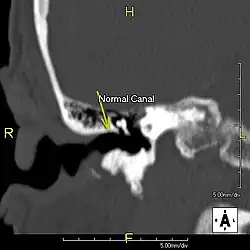

Description de cette image, également commentée ci-après

L'exostose du surfeur ou oreille de surfeur est une exostose, c'est-à-dire une croissance osseuse anormale, qui pousse vers l'intérieur du conduit auditif[1]. L'os entourant le conduit auditif réagit à l'agression thermique et mécanique de l'eau froide et de ses turbulences, par une nouvelle croissance osseuse qui a pour effet de resserrer le conduit auditif.